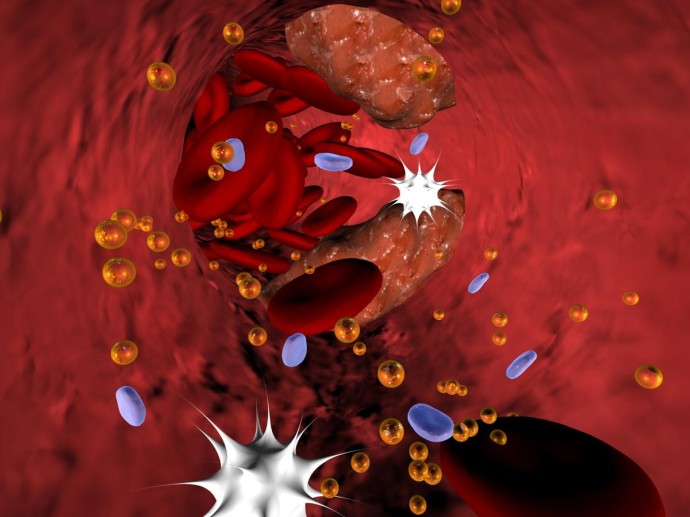

Фото: commons.wikimedia.org by Christina Lohmeyer und Sasa Ilic (SUNBEAM VISION OHG), https://creativecommons.org/licenses/by/2.5/ атеросклерозВрачи обычно выявляют атеросклероз с помощью УЗИ, ангиографии и других исследований, однако есть и домашние способы, которые помогают вовремя заметить первые отклонения и понять, что пришло время обратиться за профессиональной помощью. Они не заменяют диагноз, но дают ориентиры, позволяющие внимательнее относиться к собственному сердцу.

Как работает атеросклероз и почему важно его вовремя отслеживатьАтеросклероз формируется незаметно. Мягкие жировые образования постепенно уплотняются, кальцифицируются и ограничивают поток крови по артериям. Чем меньше кислорода получает сердечная мышца, тем выше нагрузка на организм. Поэтому давление растёт, пульс становится неустойчивым, а физическая нагрузка даётся тяжелее. Ранняя диагностика помогает не только выявить проблему, но и остановить её развитие за счёт правильной терапии и изменения образа жизни.